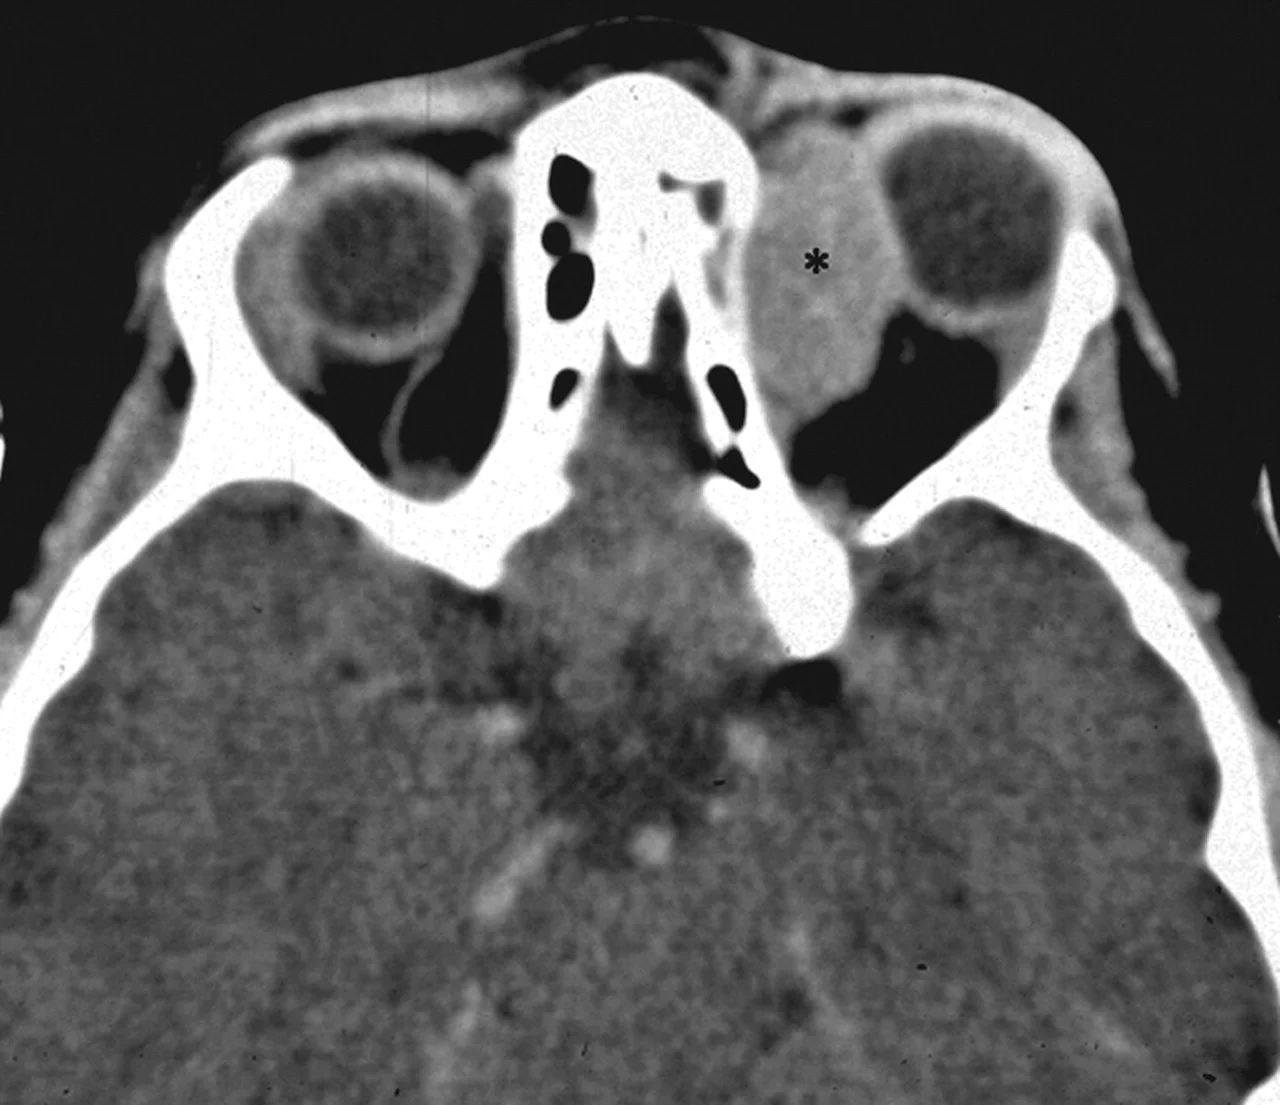

• CT Scan Image (left side)

• The child has a noticeable redness and swelling around the right eye.

• The right eye appears to be protruding.